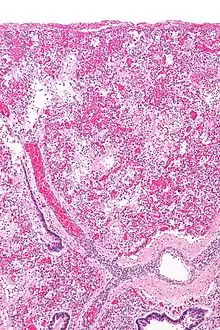

ARDS is a form of fluid accumulation in the lungs not explained by heart failure (noncardiogenic pulmonary edema). It is typically provoked by an acute injury to the lungs that results in flooding of the lungs' microscopic air sacs responsible for the exchange of gases such as oxygen and carbon dioxide with capillaries in the lungs.[12] Additional common findings in ARDS include partial collapse of the lungs (atelectasis) and low levels of oxygen in the blood (hypoxemia). The clinical syndrome is associated with pathological findings including pneumonia, eosinophilic pneumonia, cryptogenic organizing pneumonia, acute fibrinous organizing pneumonia, and diffuse alveolar damage (DAD). Of these, the pathology most commonly associated with ARDS is DAD, which is characterized by a diffuse inflammation of lung tissue. The triggering insult to the tissue usually results in an initial release of chemical signals and other inflammatory mediators secreted by local epithelial and endothelial cells.

Neutrophils and some T-lymphocytes quickly migrate into the inflamed lung tissue and contribute in the amplification of the phenomenon. The typical histological presentation involves diffuse alveolar damage and hyaline membrane formation in alveolar walls. Although the triggering mechanisms are not completely understood, recent research has examined the role of inflammation and mechanical stress.